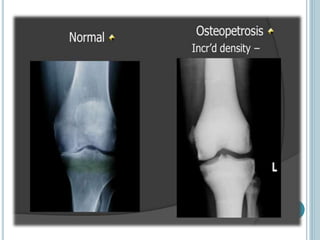

OSTEOPETROSIS

(MARBLE BONE DISEASE)

 Osteopetrosis is characterized by increased bone

density.

 primarily due to inability to resorb bone.

 This disorder is mostly observed in association with

renal tubular acidosis (due to a defect in the enzyme

carbonic anhydrase) and cerebral calcification.